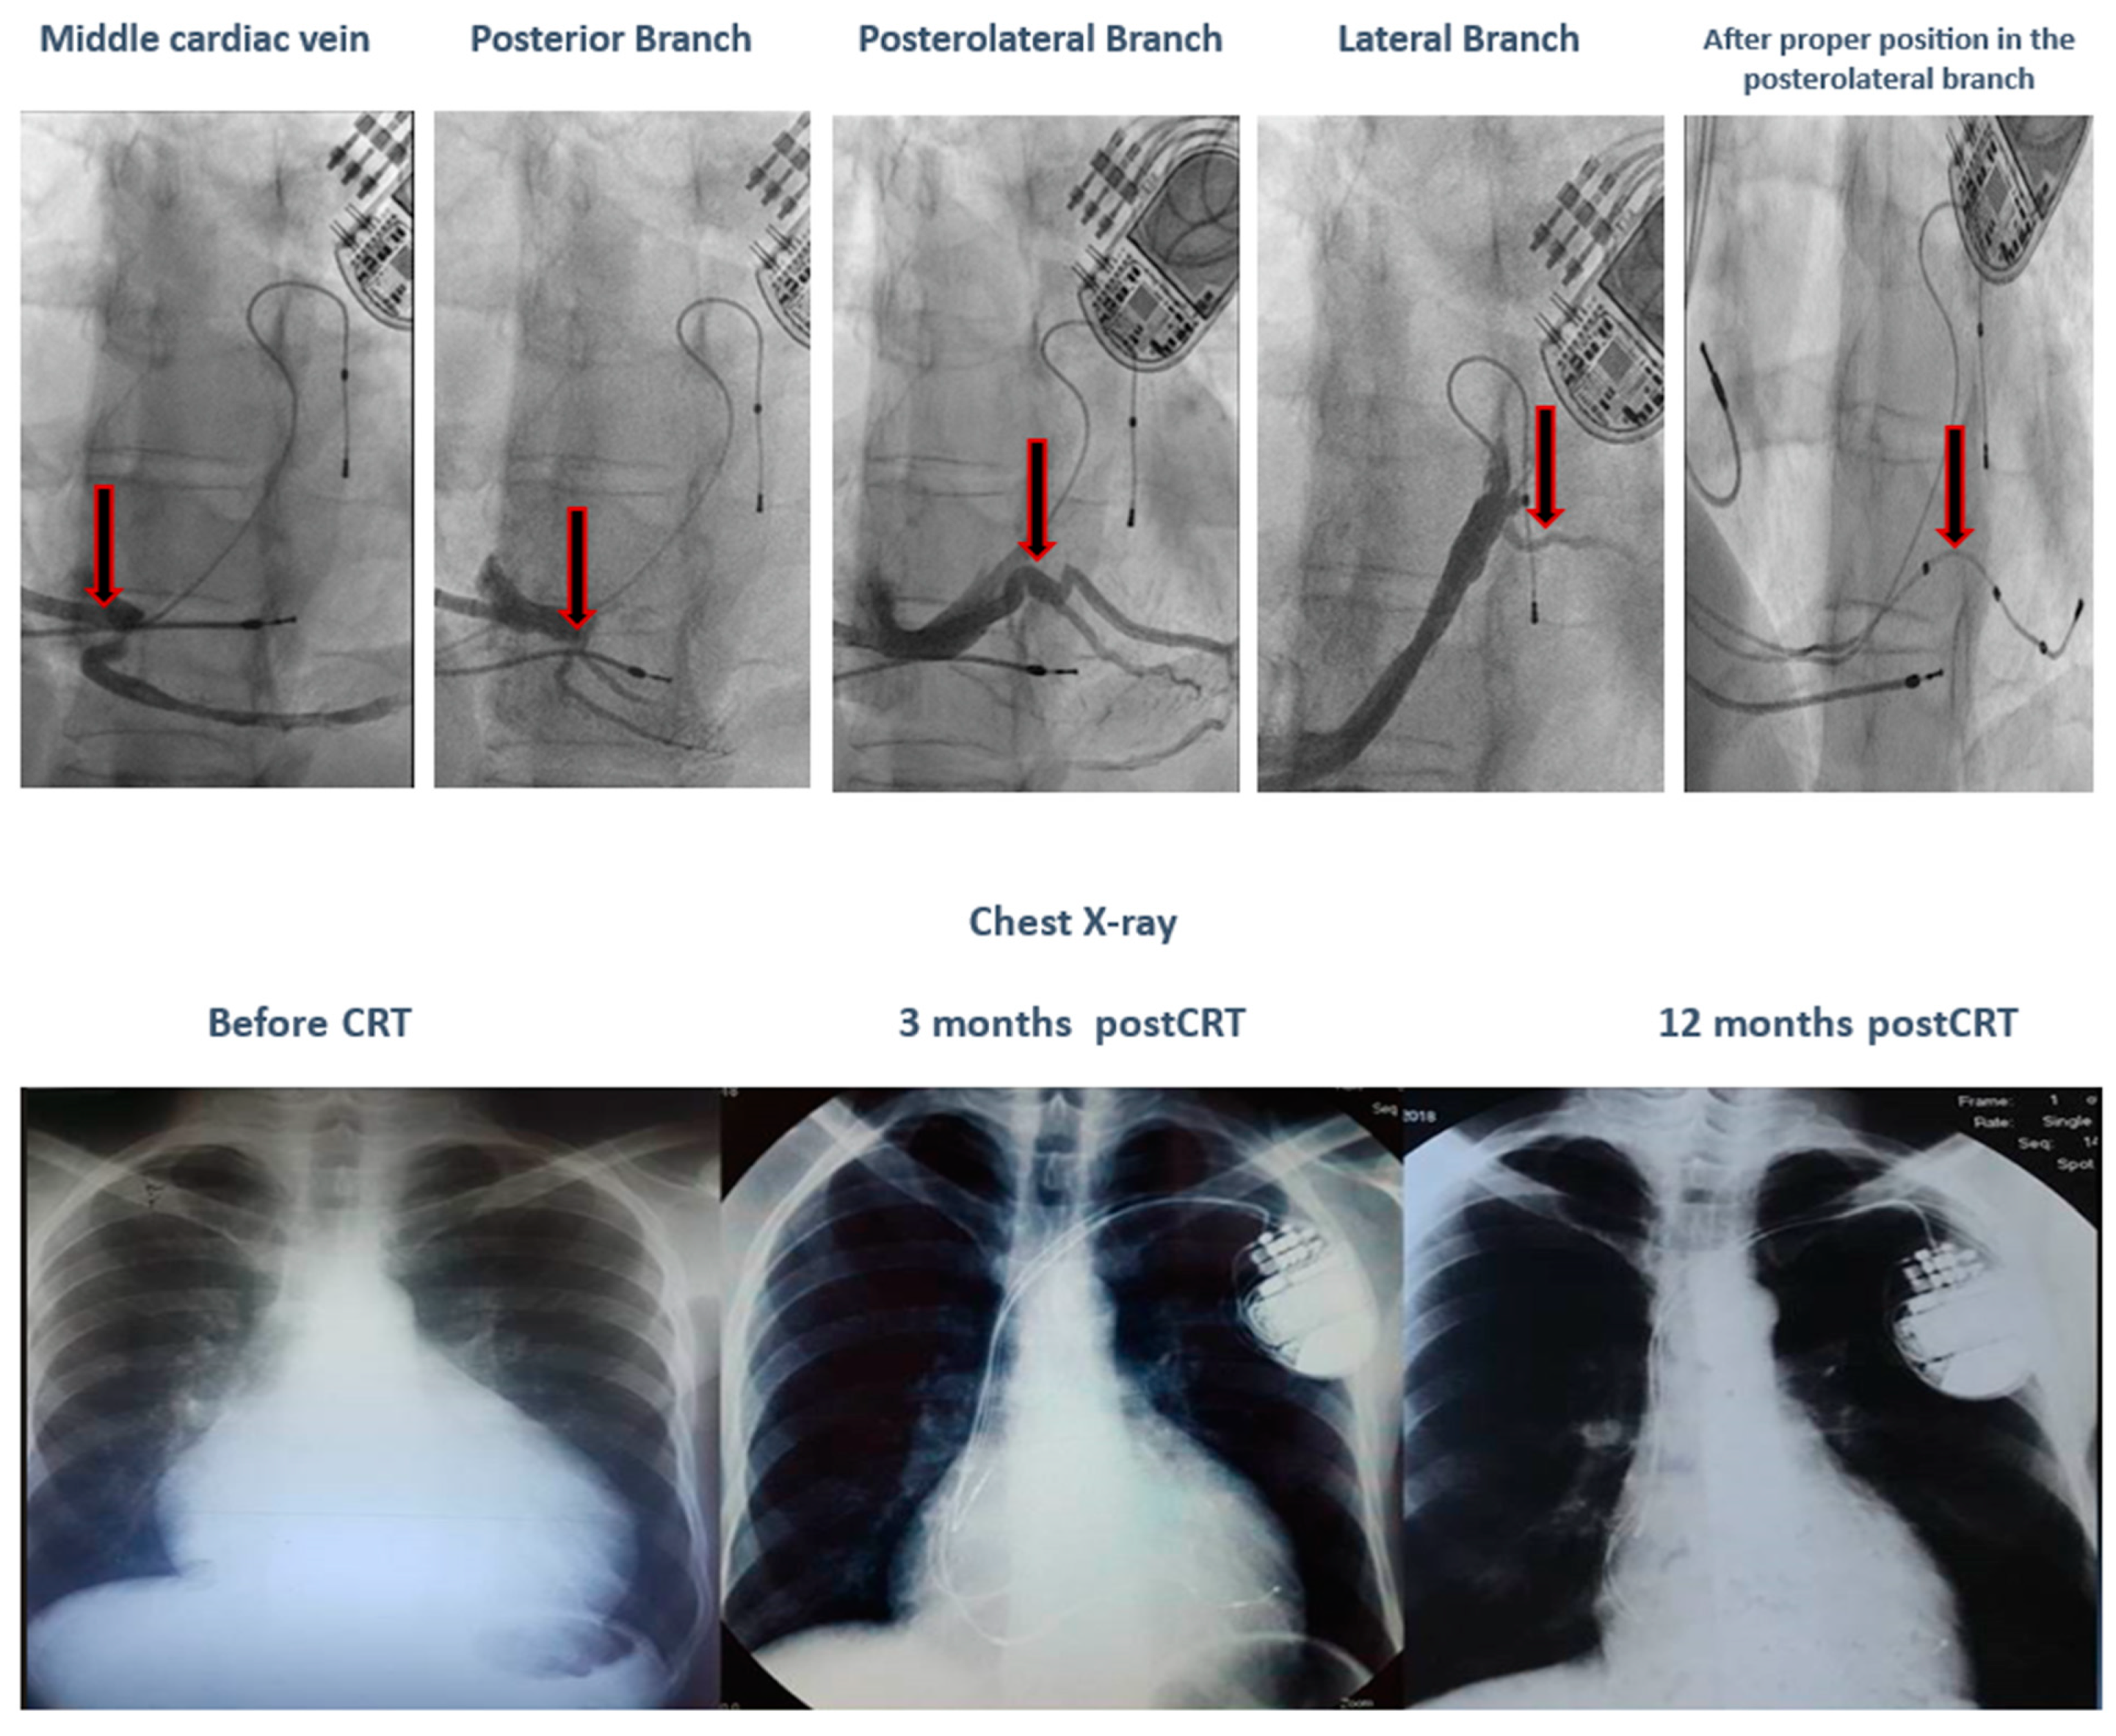

Comparing the SR vs. non-SR groups, we observe that the SR group has a younger average age, a 100% typical LBBB pattern, a wider QRS complex, and LV leads placed only in posterolateral or lateral positions. During a 12-month follow-up, none of the patients in the SR group experienced severe or moderate mitral regurgitation. In terms of genetic testing, there was a variation of mutations in the SR group, while the non-SR group had two patients with VUS-AGL and one patient with both TTN and TMEM43 pathogenic mutations. No deaths were recorded in the SR group. In the non-SR group, there was one cardiac death in the patient with both TTN and TMEM43 mutations due to refractory HF and electrical storm following a severe COVID infection, despite having the clinical and paraclinical criteria of a super-responder (nonischemic, younger age, typical LBBB pattern, wider QRS, and LV lead in the posterolateral position). Additionally, in the SR group, one patient with a TNNI3K gene mutation, who met the clinical and paraclinical criteria of a super-responder (nonischemic, younger age, typical LBBB pattern, and wider QRS) on maximal medical treatment, was initially a non-responder due to the inadequate positioning of the LV lead in the anterior wall. After proper positioning in the posterolateral wall, the patient became a super-responder, as illustrated in Figure 3.

Figure 3.

The evolution of a patient with a TNNI3K gene mutation after proper positioning of the LV lead in the posterolateral wall.

Conversely, a patient with a TNNI3K gene mutation, who met the super-responder criteria (nonischemic, younger age, typical LBBB pattern, and wider QRS) on maximal medical treatment, was initially a non-responder due to the inadequate positioning of the LV lead in the anterior wall. After proper positioning in the posterolateral wall, the patient became a super-responder.